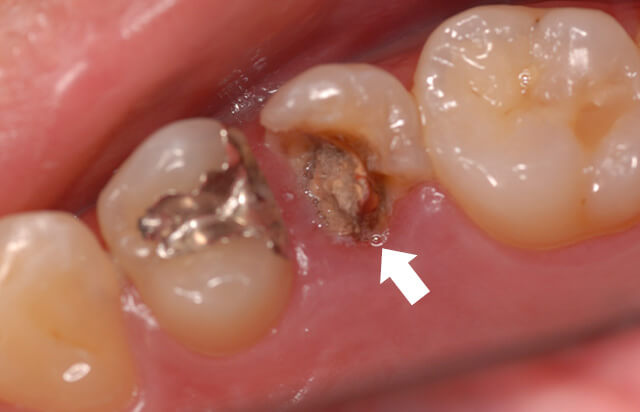

初診時の状態

神経を除去した歯の詰め物が脱落して来院されました。隣接面より2次的な虫歯が進行し内面から重度の虫歯に罹患していました。詰め物が取れた歯は、重度の虫歯でも痛みを感じないので、このように歯肉辺縁より深い虫歯になることがあります。

虫歯を除去すると、写真のように切り株のようになってしまいます。一般的に残根と言われる状態なので抜歯が適応ですが、部分矯正を応用し歯根を引っ張り出すことで改善できることがあります。このまま被せ物を装着すると、歯周炎を引き起こしてしまうこともあります。